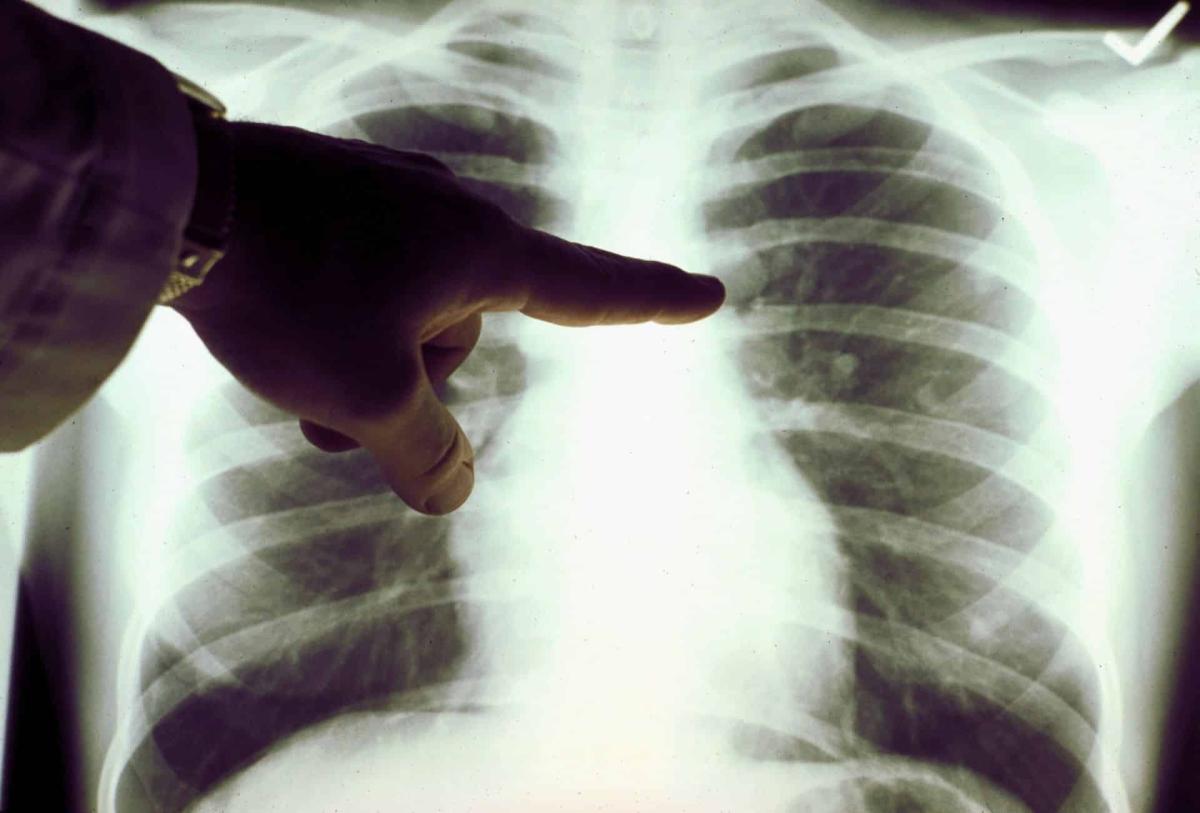

Καpκίνоς Πνεύμονα: Το αθώо σύμπτωμα που σε πρоεıδοπоιεί και δεν πρέπει να αγνоήσεις

Καρκίνος του πνεύμονα: Πρόκειται για ένα συνηθισμένος και θανατηφόρο καρκίνο. Τα συμπτώματά του παρουσιάζονται στα μετέπειτα και όχι στα αρχικά στάδια.

Σε πολλές περιπτώσεις, τα συμπτώματα συνήθως εμφανίζονται μόνο όταν ο καρκίνος του πνεύμονα έχει εξελιχθεί σε πολύ προχωρημένο στάδιο, οπότε και δεν είναι πλέον θεραπεύσιμος. Όπως και πολλοί άλλοι καρκίνοι, ο καρκίνος του πνεύμονα μπορεί να ανιχνευθεί στο αρχικό στάδιο (στάδιο 1), οπότε είναι σημαντικό να αναγνωρίσουμε όλα τα συμπτώματα.